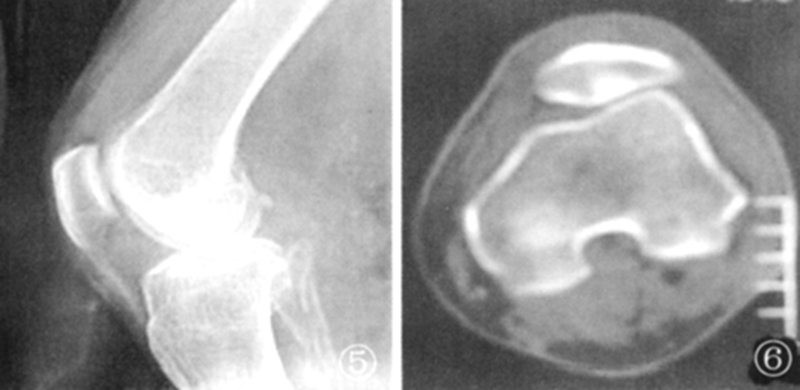

髌骨软骨软化平片及CT表现:膝关节侧位片示关节间隙变窄, 关节缘皮质线有中断。CT示髌股关节略有错位,关节间隙变窄,软骨下骨质密度增高